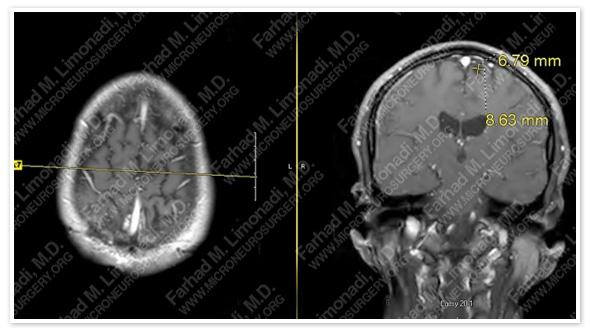

MRI scan of the patient’s brain showed a dural-based tumor in the right frontoparietal region with local mass effect on the brain. This was the tumor that had been treated with Gamma Knife 3 years prior.